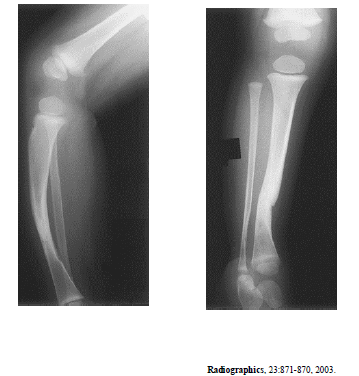

As radiografias acima são de um paciente do sexo feminino com um ano de idade. Com base nessas radiografias, é correto afirmar que

a porção identificada do fêmur tem aspecto normal.

As radiografias acima são de um paciente do sexo feminino com um ano de idade. Com base nessas radiografias, é correto afirmar que

as imagens revelam esclerose cortical no terço inferior da tíbia.

As radiografias acima são de um paciente do sexo feminino com um ano de idade. Com base nessas radiografias, é correto afirmar que

o raquitismo pode apresentar alterações semelhantes.

As radiografias acima são de um paciente do sexo feminino com um ano de idade. Com base nessas radiografias, é correto afirmar que

o principal diagnóstico é tibia vara (doença de Blount).

As radiografias acima são de um paciente do sexo feminino com um ano de idade. Com base nessas radiografias, é correto afirmar que

esse quadro radiológico pode ser justicado por neurofibromatose.

As radiografias acima são de um paciente do sexo feminino com um ano de idade. Com base nessas radiografias, é correto afirmar que

o paciente não possui a patela.